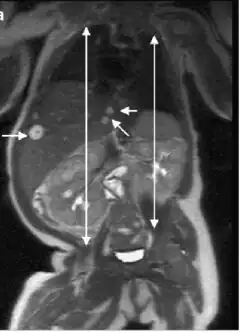

| Adrenal gland: Beckwith-Wiedemann syndrome Nuclear enlargement and hyperchromasia with nuclear "pseudoinclusion" near the center of field. Mitotic figures were not identified. | |